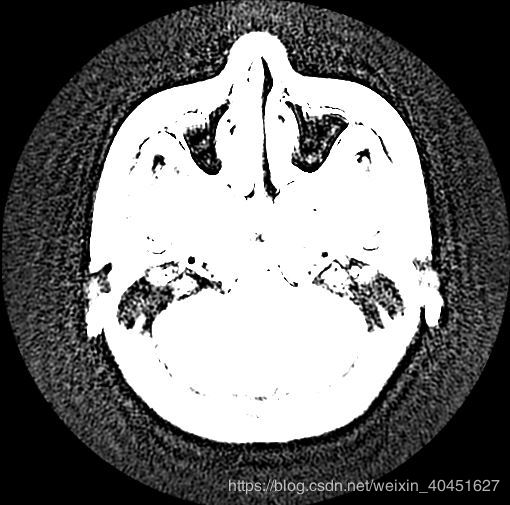

一條指令即可,但是效果很差,如圖所示:

綜合來看,兩種方法都不是很好.